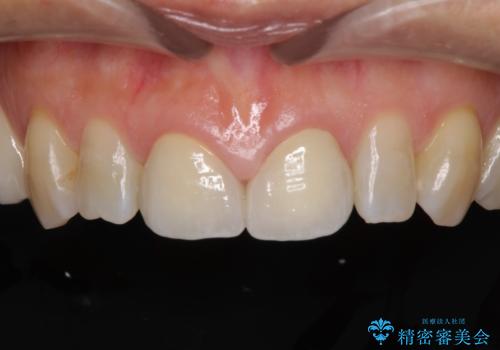

前歯のすきっぱ&奥歯の虫歯 セラミッククラウンで徹底的に治す

今回はまず欠けた場所を修復して見た目を回復させたのち、ラミネートべニアの仮歯をつくり、しばらく使用して考えて頂きました。メリットやデメリットを説明した結果、外れにくいセラミッククラウンをご選択頂きました。

咬み合わせや元のご自身の歯の色に特徴があったため、セラミッククラウンを修正したり、隣の歯を金属を外して白いつめものに変えたりして経過観察を長めに行いました。

患者様には大変満足して頂きました。